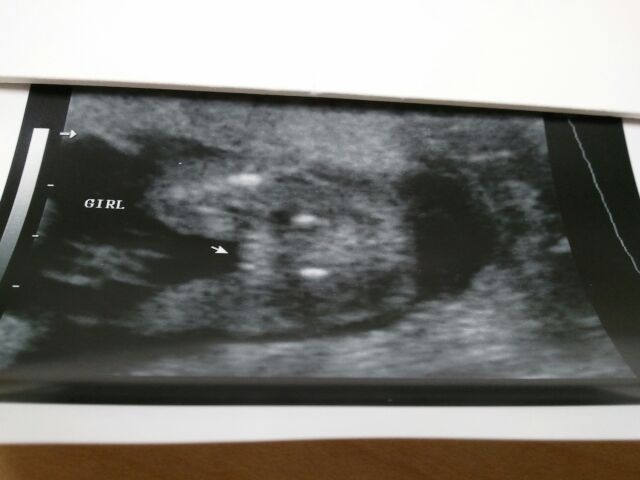

These are my baby girl's U/S pictures at 18w5d.

So that potty shot is definitely girl, right? I know it's a girl, but I just need some reassurance!!